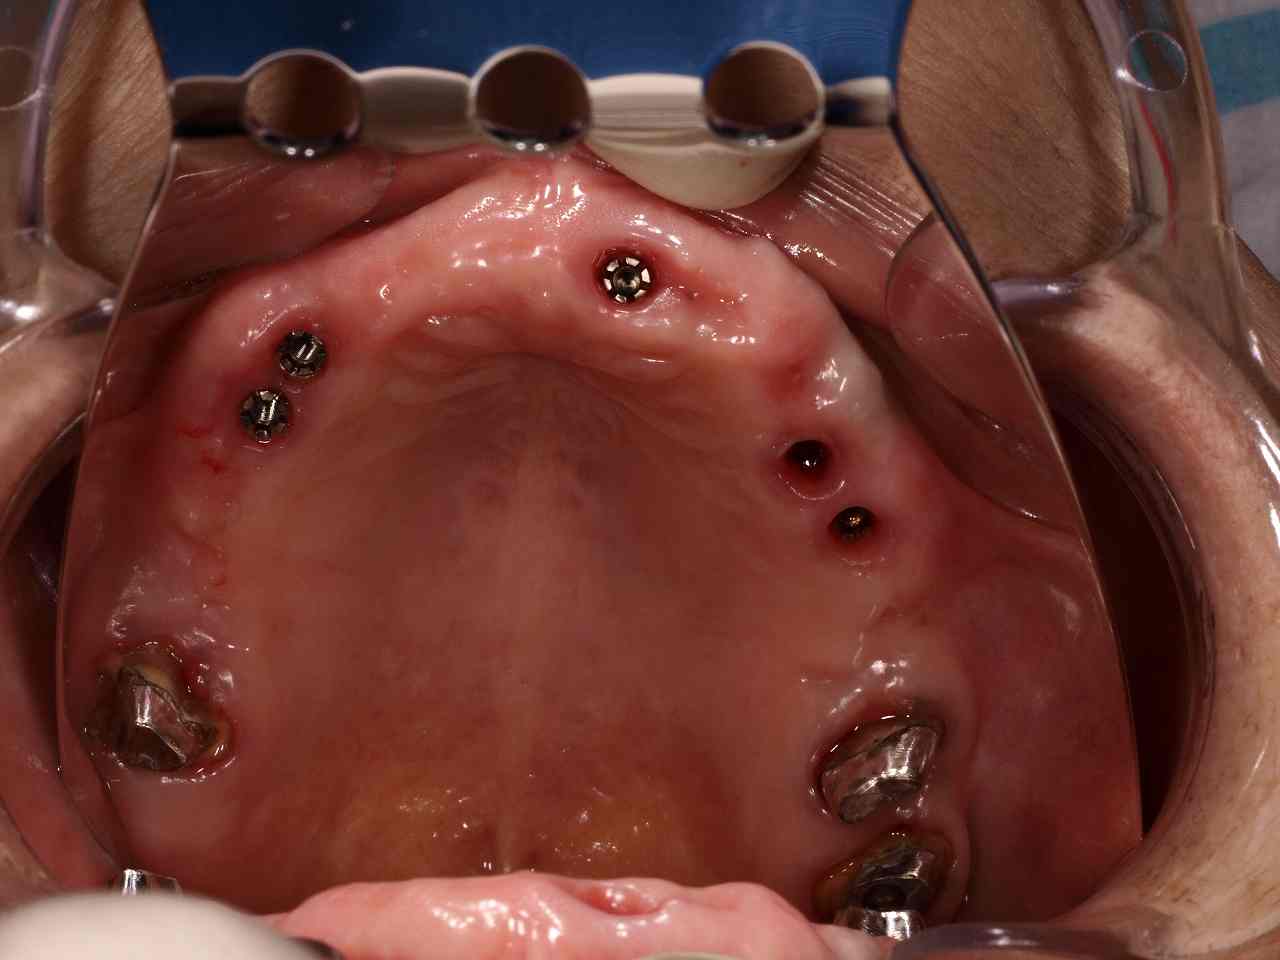

口腔内になります

口腔内はこのような状態になります

天然史3本とインプラント5本にてブリッジで作成していきます

口腔内になります